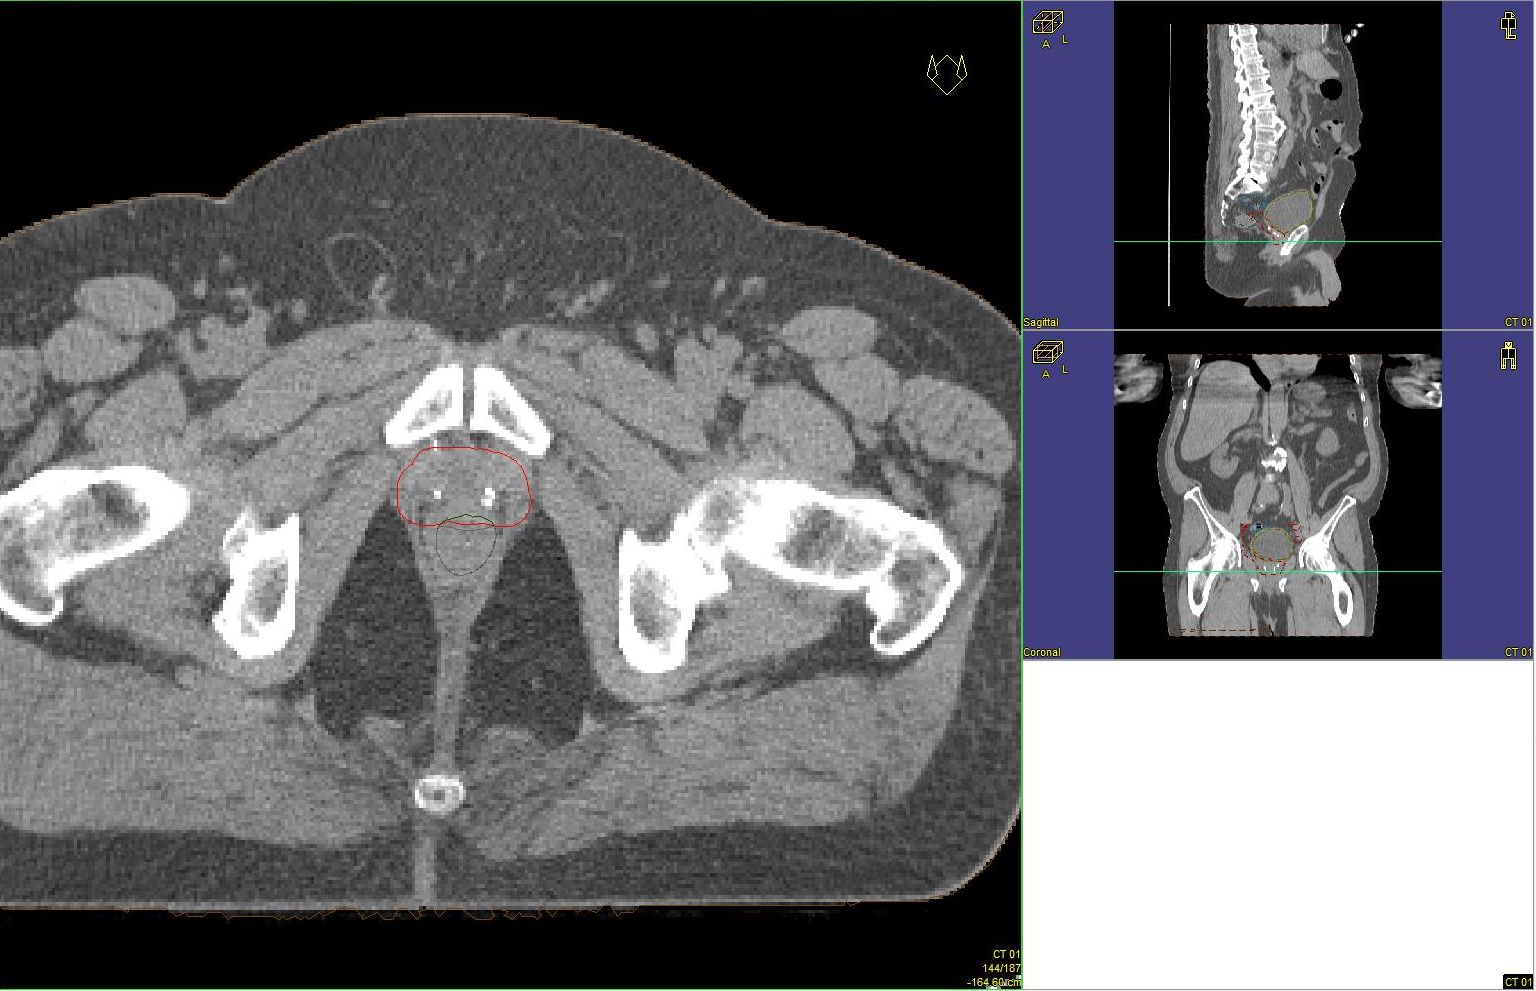

Prostata-Ca: Zielvolumen der postoperativen Radiotherapie

Beispiel: postoperative RT